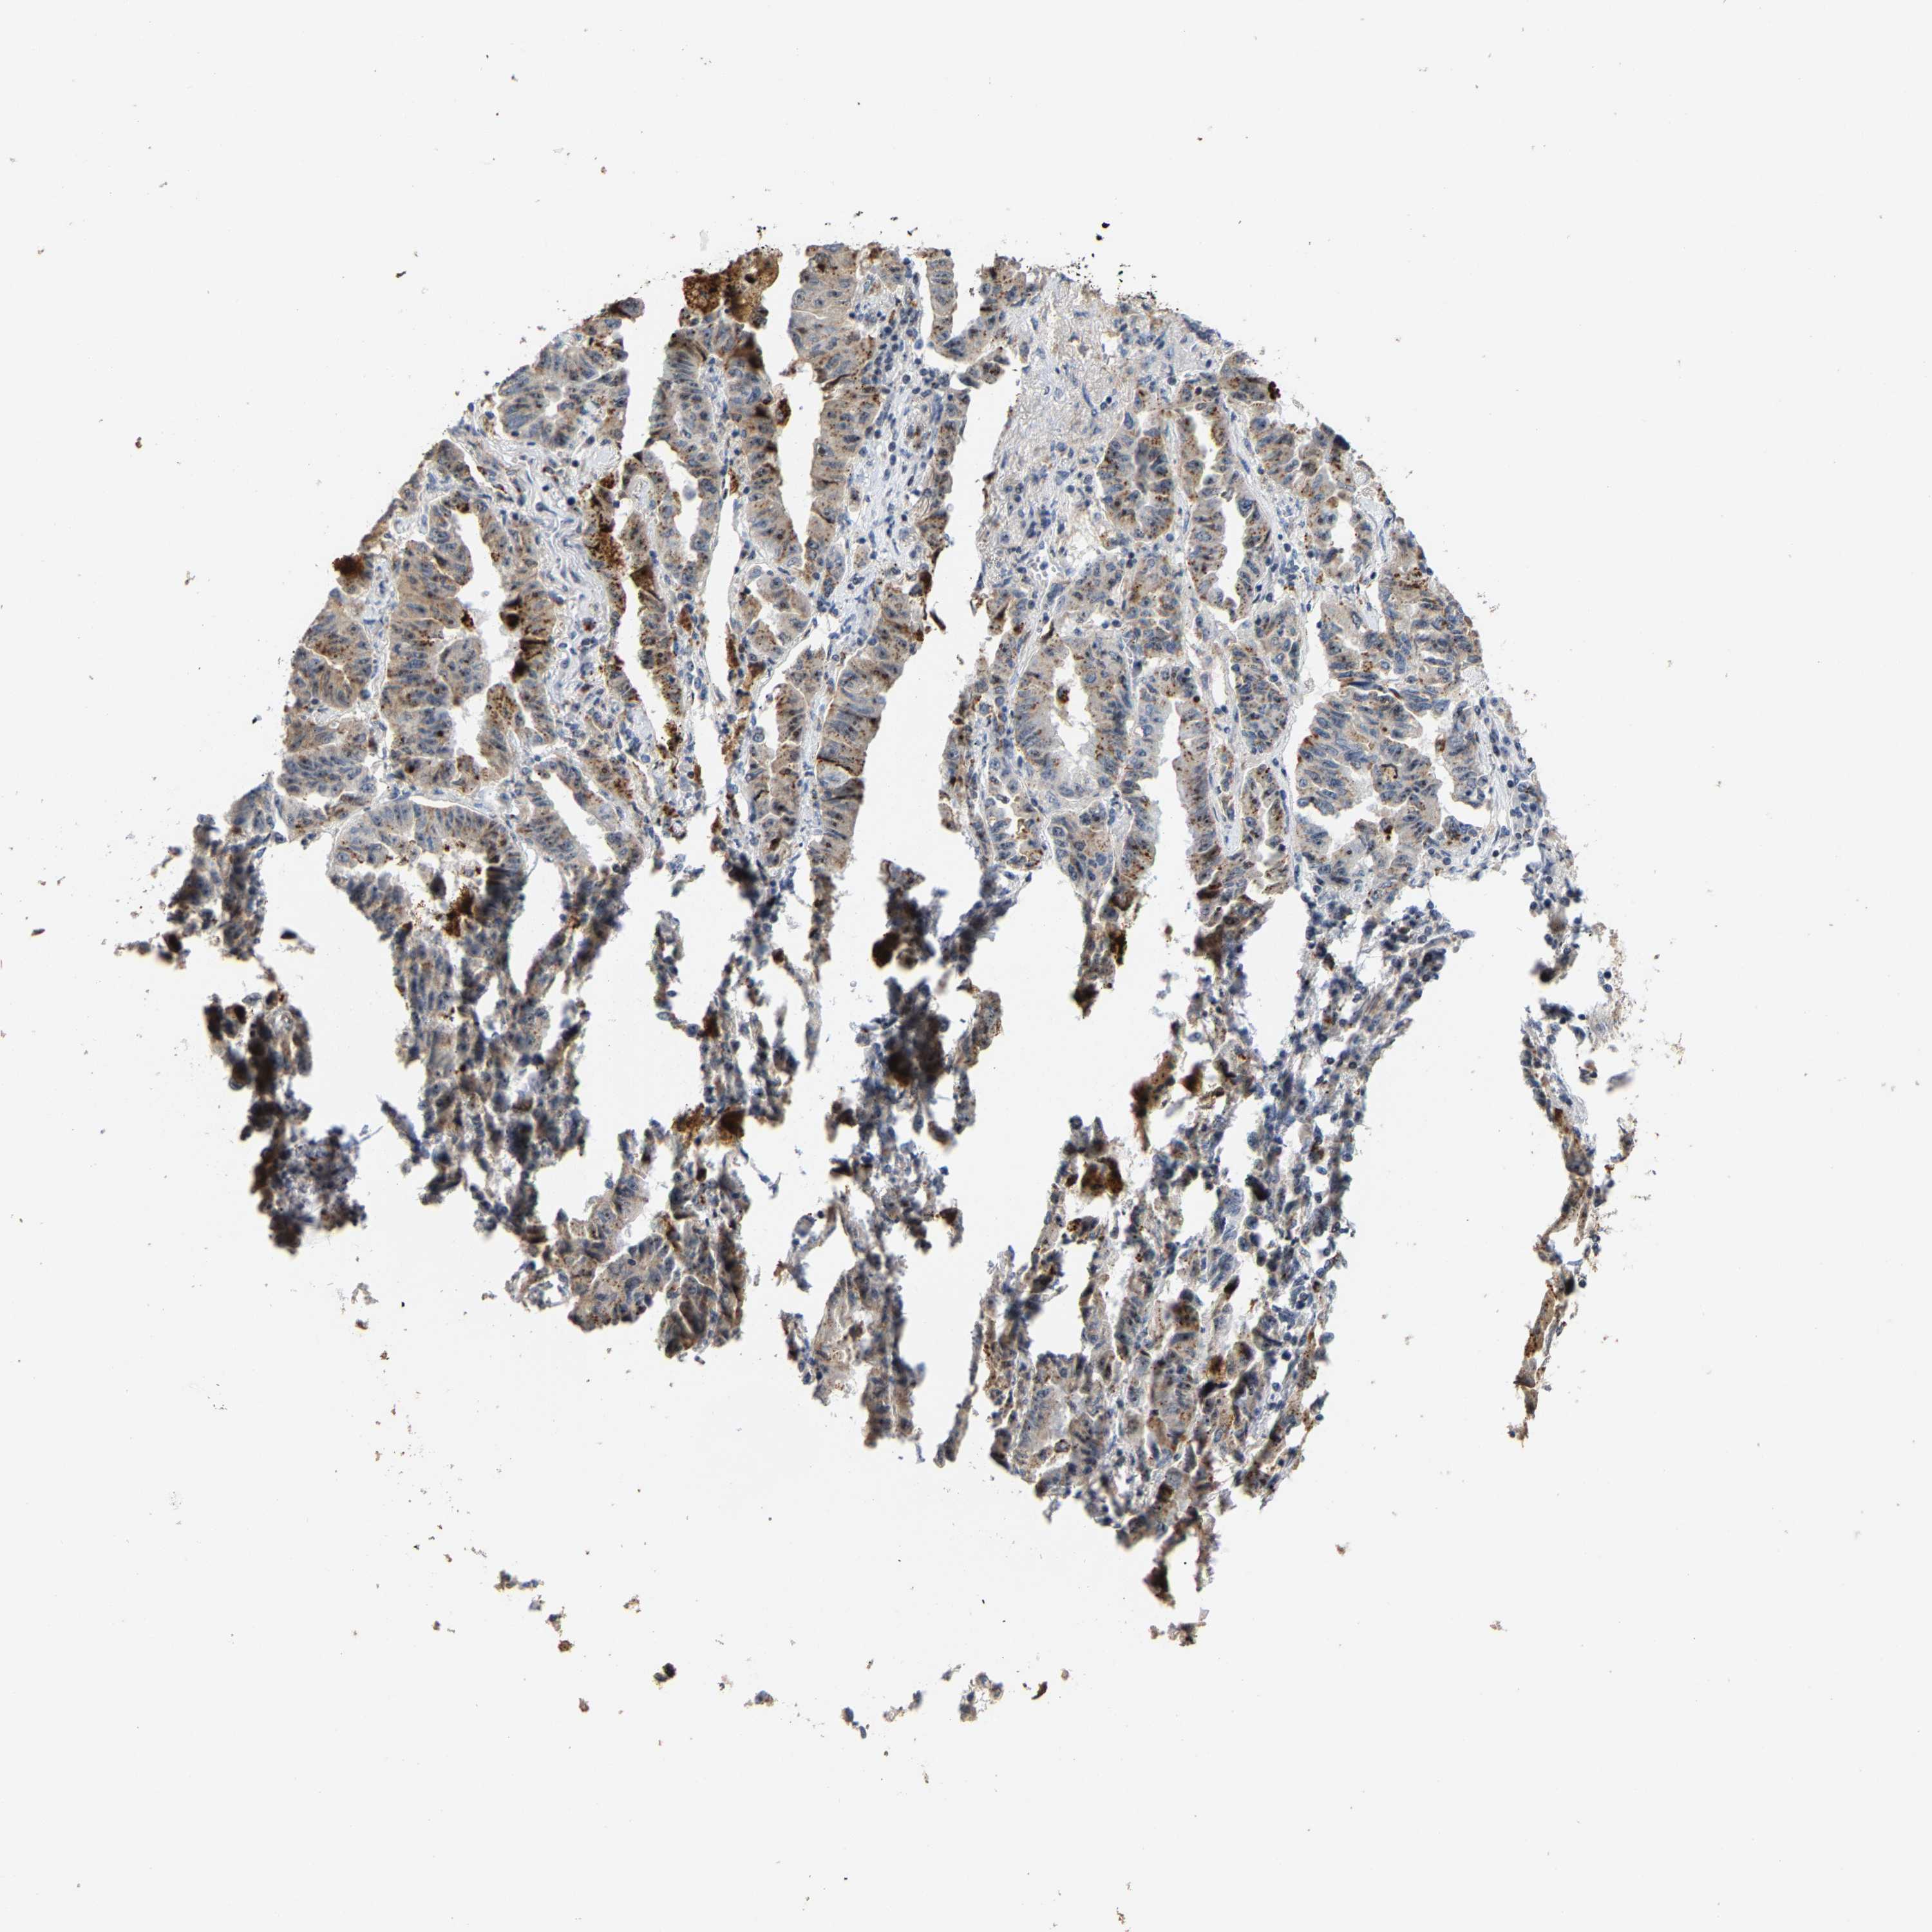

CANCER LUNG CANCER Show tissue menu

LUAD TCGA LUAD VALIDATION LUSC TCGA LUSC VALIDATION PROTEIN LUAD CPTAC PROTEIN LUSC CPTAC PROTEIN EXPRESSION